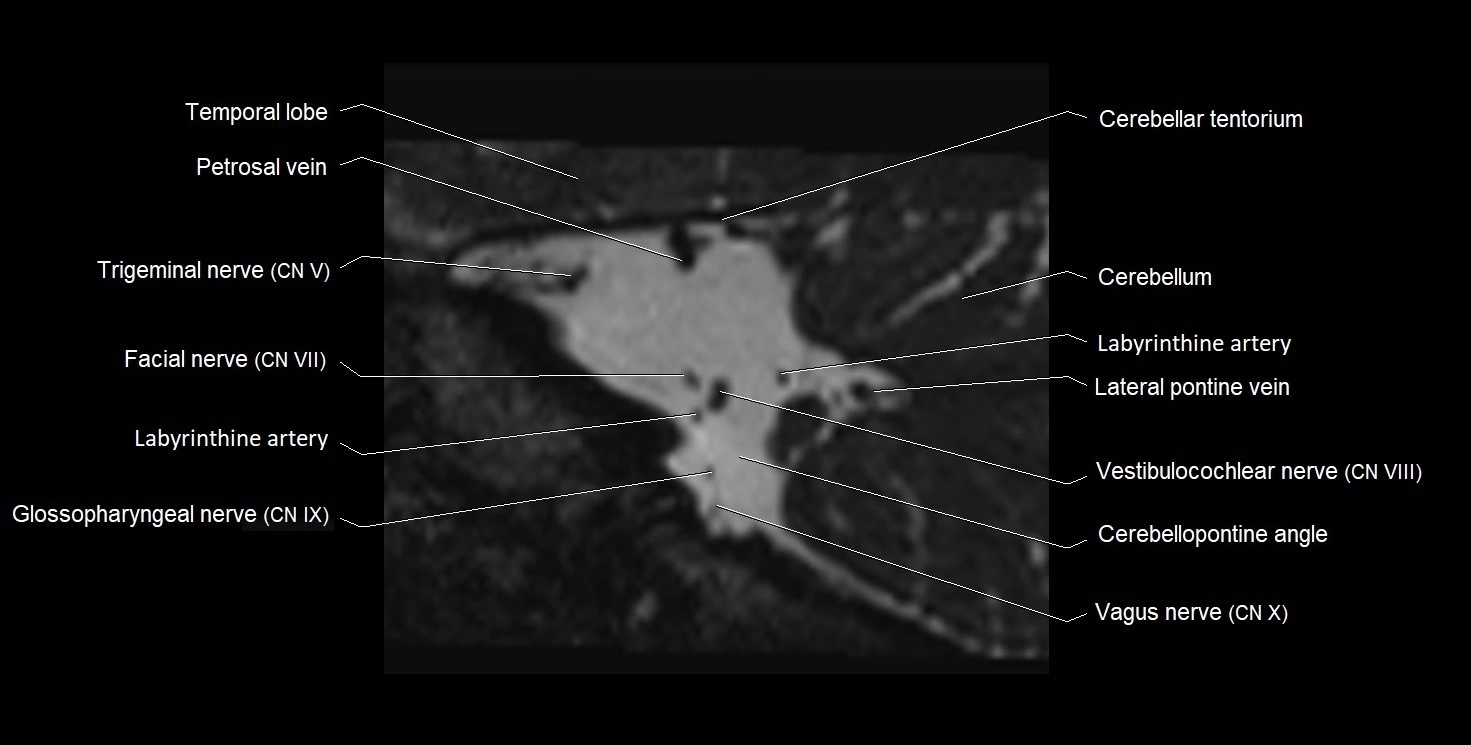

MRI Appearance

• The abducens nerve is a small, thin, linear structure

• Best visualized on high-resolution T2-weighted 3D MRI sequences (e.g., FIESTA or CISS)

• Seen as a hypointense (dark) line running from the brainstem at the pontomedullary junction, traversing the prepontine cistern, and entering Dorello’s canal under the petrosphenoidal ligament, then into the cavernous sinus, and finally the orbit

• May be challenging to visualize in standard MRI due to its small size

• Pathology may be inferred by absence, displacement, or enhancement of the nerve